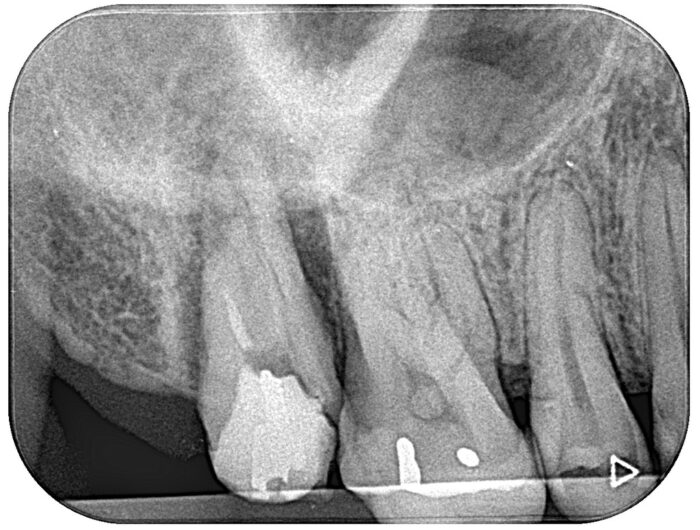

40代男性の患者さまです。

右上の奥歯(右上7)が割れているため、抜歯が必要と診断されて来院されました。

精査を行った結果、歯の再植による保存を試みる方針となりました。

まず、できる限り低侵襲に抜歯を行い、口腔外で必要な処置を実施しました。

根管内のガッタパーチャを除去

破折片をスーパーボンドで接着固定

その後、元の位置へ再植し、適切な固定を行いました。

術前